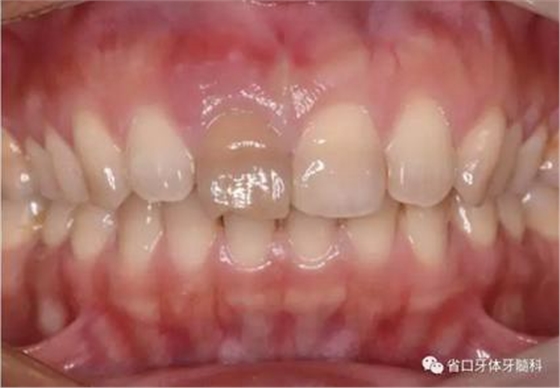

1.?病例簡介 43歲女性患者,主拆:右上前牙松動不適數(shù)日要求修復(fù)。現(xiàn)病史:患者數(shù)年前右上前牙因“齲壞”于外院行根管治療(具體不詳),數(shù)日前牙冠松動不適,現(xiàn)覺影響咀嚼及美觀,遂來我院要求進(jìn)一步診治。否認(rèn)高血壓、心臟病等重大疾病,否認(rèn)結(jié)核、肝炎等傳染病史,否認(rèn)手 術(shù)、輸血史等,未發(fā)現(xiàn)藥物過敏。無吸煙習(xí)慣。臨床檢查:口外觀顏面基 本對稱,皮膚無紅腫破潰,顳下頜關(guān)節(jié)區(qū)無彈響、雜音、壓痛,開口度約 37mm,開口型“↓”,頜下、刻下和頸部未及腫大淋巴結(jié)。中位笑線??趦?nèi)檢查,口腔衛(wèi)生可,色素(+),BOP(-),PD=2mm,上頜右側(cè)中切 牙冠部變色,冠根折斷至齦下3mm,叩不適,松動Ⅱ°~Ⅲ°。牙齦稍紅, 齦緣水平及齦乳頭高度可,屬于中厚齦生物型,附著齦寬度約5mm,唇系帶附著可。上頜右側(cè)中切牙缺牙間隙與對側(cè)同名牙一致,約>7mm,修復(fù)空 間良好。與對頜牙覆合覆蓋正常。MCT檢查示上頜右側(cè)中切牙冠根折斷至骨 下,根管內(nèi)見充填物,根充不全,根尖見陰影,大小約3mm×3mm。牙槽窩根方可用骨量可,唇側(cè)骨壁完整,冠方骨壁厚度約1mm。

圖1 術(shù)前口內(nèi)照

圖2 術(shù)前口內(nèi)照

圖3 術(shù)前口內(nèi)照